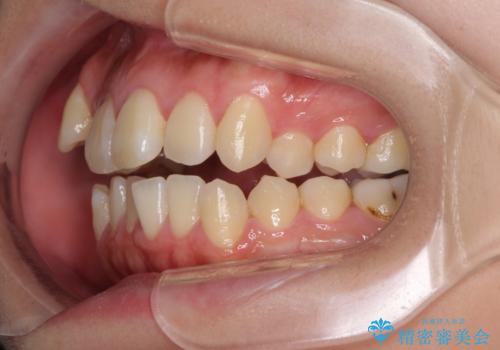

- 八重歯と叢生を気にして来院された患者様です。

上下の前歯が非接触であり、叢生や八重歯が顕著であったため、上顎左右第一小臼歯2本を抜歯して排列することとしました。

抜歯により移動量が多くなるため、ワイヤーや補助装置を活用し、その後インビザラインによる矯正治療を行うこととしました。

元々奥歯に負担のかかる咬み合わせですり減っていたため、仕上がった歯並びでも奥歯が咬んでいないように見えましたが、実際にはしっかりと咬合しており、患者様本人も咬んだ感触に違和感はないとのことでした。